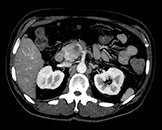

Выполните просмотр требуемой области с помощью нескольких решений благодаря эксклюзивному приложению Spectral Magic Glass для вычленения данных о составе тканей.

Здесь представлена серия изображений, на которых значения воксела обозначают эффективное атомное число. Эффективное атомное число может быть дробным, обозначающим какой-либо элемент, соединение или смесь. Данное число может отличаться от порядкового номера, указанного в периодической таблице. Единица для обозначения — Z.